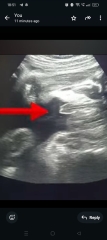

DramaAlpaca · 30/07/2025 22:12

Looks like a boy to me.